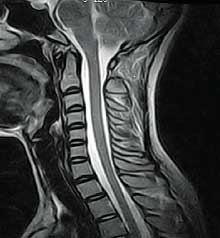

– Me duelen “las cervicales”. Me han dicho que tengo dos protrusiones discales en la Resonancia y que el dolor proviene de ahí. Mi panorama es más bien negro. Me veo en una silla de ruedas…

El terapeuta cognitivo probablemente juzgará como catastrofista la previsión del paciente e intentará rebajar el tono alarmista de las previsiones pero dejará intacta la creencia de que el dolor proviene de “las cervicales”, de las protrusiones detectadas en la Resonancia.

La conclusión que se desprende de que el dolor proviene de “las cervicales” dado que 1) duele sobre el cuello y 2) se ven unos discos que protruyen, probablemente es errónea ya que no es condición necesaria ni suficiente la protrusión discal o cualquier signo “degenerativo” artrósico para explicar el dolor.

Lo único que podemos afirmar es que “el cerebro valora el cuello como una zona amenazada de necrosis”. Dado que no existen evidencias de necrosis consumada o inminente (la protrusión discal no contiene, en absoluto, esa amenaza) el dolor proviene de una evaluación catastrofista cerebral sobre vulnerabilidad en el cuello. Este catastrofismo está alimentado por la información profesional que atribuye al hallazgo de la Resonancia un valor causal.

La “falsa creencia” debe ser disuelta pero no parece sensato cargar sobre el Psicólogo la responsabilidad de juzgar si lo que el padeciente cree sobre su cuello es correcto o catastrofista. La falsa creencia debe etiquetarse como tal desde el conocimiento disponible sobre correlación entre protrusiones discales y dolor (no existe esa correlación) y sobre neurobiología del dolor (la importancia de las creencias y expectativas).